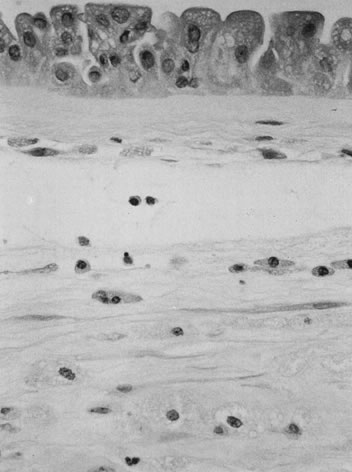

The initial histopathology of meconium passage is individual amnion epithelial cell necrosis, followed by amnion hyperplasia, pseudostratification, and vacuolation (Fig. 6), over an unknown time frame. Meconium is phagocytosed by macrophages in the amnion and chorion and eventually cleared from the amnion fluid. What time is required to clear meconium from the amniotic fluid and whether meconium is ever removed from cells of the extraplacental membranes are unknown.

Fig 6. Meconium-induced injury of the amnion, resulting in hyperplasia. Also note the numerous, foamy, pigmented macrophages within the amnion and chorion (hematoxylin and eosin, ×40).